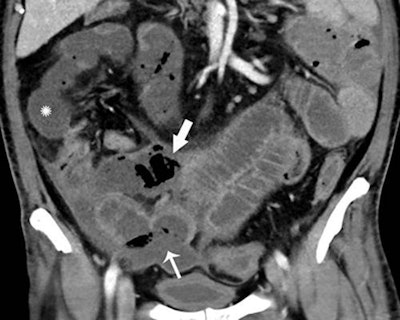

Of these patients, 31% of the CT scans -- representing 3.2% of all patients -- showed bowel abnormalities. These bowel abnormalities, which included thickening and findings of ischemia such as pneumatosis and portal venous gas, were more frequently experienced in intensive care unit (ICU) inpatients, according to the researchers. Surgical correlation in four patients revealed unusual discoloration of bowel in three of the patients and bowel infarction in two patients.

In two of the patients who had bowel resection, pathology results showed ischemia with patchy necrosis. Both of the patients had fibrin thrombi in submucosal arteries, suggesting that the bowel ischemia was caused by these thrombi, according to the researchers.

"Some findings were typical of bowel ischemia, or dying bowel, and in those who had surgery we saw small vessel clots beside areas of dead bowel," Bhayana said in a statement from the RSNA. "Patients in the ICU can have bowel ischemia for other reasons, but we know COVID-19 can lead to clotting and small vessel injury, so bowel might also be affected by this."